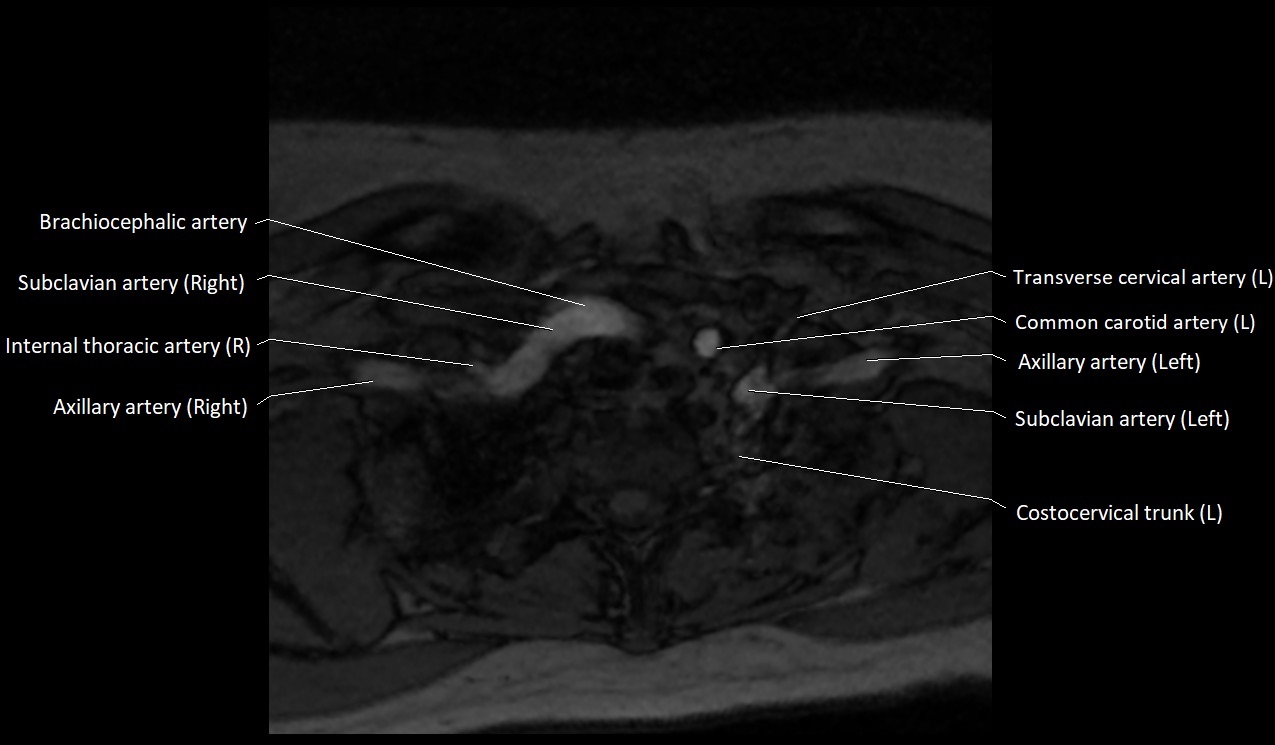

MRI images

image